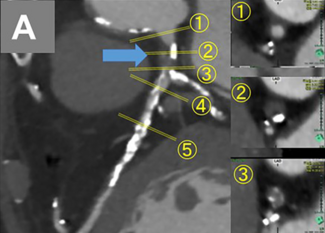

A 59-year-old man with exertional angina and coronary angiography showing chronic total occlusion of the right coronary artery with collateral filling from the left anterior descending artery. Dual injection revealed an ambiguous proximal...

Tarek Abdeldayem, MD; Mustafa Tigen, MD; Omer Gogtekin, MD; Mohaned Egred, BSc (Hons), MB, ChB, MD, FRCP, FESC

Video Supplement to "Controlled Antegrade and Retrograde Tracking (CART) Technique Via Epicardial Collaterals: Feasible and Safe" (Clinical Image).